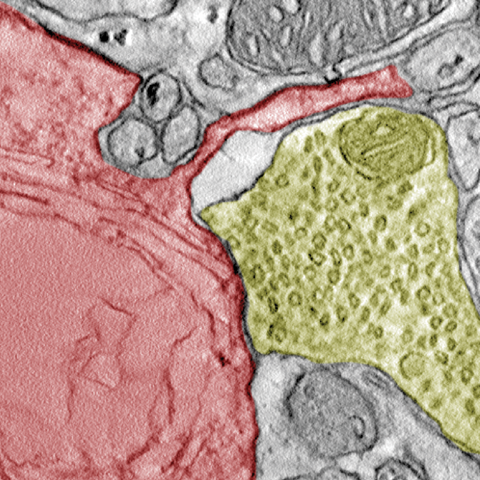

Elektronenmikroskopische Aufnahme von einer Krebszelle (rot) und einer Nervenzelle (gelb).